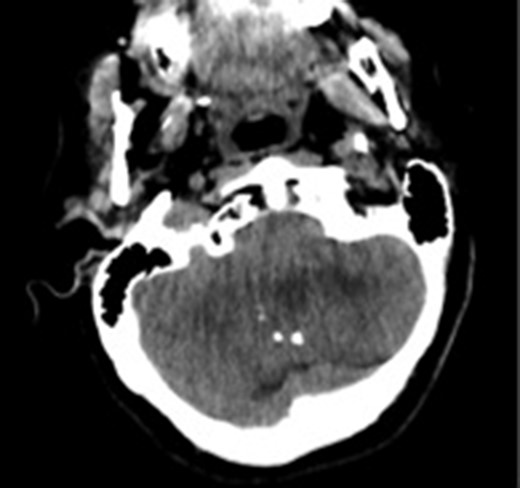

A 55-year-old woman presented with headache, dizziness and gait imbalance for 2 months. Patient’s history revealed a posterior fossa tumor that had been diagnosed 4 years ago prior to admission to our clinic. At that time, contrast enhanced of magnetic resonance imaging (MRI)showed the ill defined lesion, 5.5×3.5×4 cm in size without perilesional edema (Fig. 1A,B). During this 4 years period, her follow-up had been performed with serial MRI (Fig. 2A and B) and CT assessments (Fig. 3). Until 2 months ago, she had only intermittent headache. On neurological examination, she had cerebellar signs including ataxia and also bilateral papilledema through ocular investigations. CT assessment showed punctate calcified lesion demonstrated with undifferentiated margins of the lesion from the cerebellar parenchyma. The last MRI findings showed heterogeneous ill defined lesion without perilesional edema in vermis and extending to the adjoining cerebellar hemisphere at the supracerebellar infratentorial space with a dimension of 6.7×4×4 cm size causing compression of the fourth ventricle and marked hydrocephalous. The patient underwent surgery through a midline supracerebellar infratentorial approach in the prone position. It was a soft whitish intra-axial tumor, moderately vascular with a good plane between the vermis and cerebellum. A complete resection was achieved. The cerebrospinal fluid shunt was not decided to be placed (Fig. 4). Pathological diagnosis was reported as CLN. Immunohistochemical study, synaptophysin and neuron-specific enolase (NSE) immunopositivity were found (Fig. 5). In the mean time, glial fibrillary acidic protein (GFAP) was immunonegative and Ki-67 index was 2%. After operation, she had uneventful postoperative period and was discharged on seventh day.

Computed tomography image showing calcifications in the lesion. The margins of the lesion cannot be differentiated from cerebellar parenchyma.

CLN is a rare central nervous system tumor mostly affecting adult population. It was defined as a neuronal-glial tumor in the 2016 World Health Organization (WHO) classification [1, 2]. Based on the current literature, precise radiologic features and biological behaviors of these tumors are still unclear. Radiological characteristics of CLN cannot be differentiated from adult medulloblastomas and ependymomas preoperatively. There were restricted number of cases about the CT and MRI features of these tumors in the literature [2, 6]. CT shows hypo-iso-or hyperdense ill-defined or well-defined variable contrast enhanced lesions with focal areas of marked hypodensity due to fatty tissue [6]. Our case might be suggested as unique for the CT appearance that had included multiple intratumoral calcifications without fat density appearance which made this tumor more challenging in differantiation from the ependymomas. To the best of our knowledge, there were no reported calcified CLN on CT images in the English literature. Big sized tumors without peritumoral edema and low attenuating fatty tissue might be predictable for CLN through the MRI findings for posterior fossa tumors as our case. CLN may recur with a mean interval of 8.5 years [7]. The related literature shows 5-year survival rate postoperatively as 48%, the recurrence up to 40% [8]. To date, most published cases proliferation index as measured by Kİ-67/MIB-1 was usually low (<5%). The tumor with high rates of Ki-67 was associated with high rates of recurrences and more agressive biological behavior [9, 10]. In our case, despite the big size of the lesion in the initial MRI (5.5×3.5×4 cm), the growth pattern of the tumor was quite slow. However, radiological enlargement had been measured only 1.2 cm on sagittal plane and 0,5 mm in antero-posterior direction (6.7×4×4 cm) during preoperative 4 years period. In the present case, slow tumor progression rate was related to low Ki-67 index which was found as 2% after total tumor resection. To the best of our knowledge, this is the first nonoperated big CLN patient in the literature who survived for a long time with a very slow tumor progression.